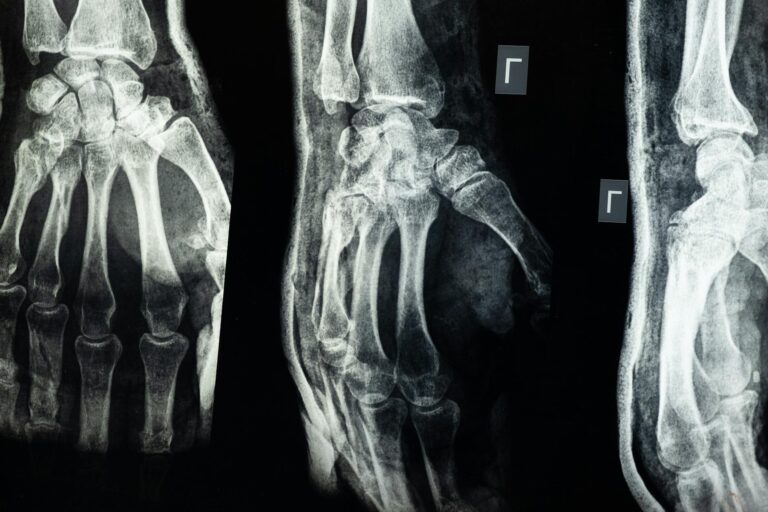

Radiografía de Edad Ósea: Desmitificando el Crecimiento y Desarrollo Infantil en Puente Alto

Imagenología Radiografía de Edad Ósea: Desmitificando el Crecimiento y Desarrollo Infantil en Puente Alto ¿Preocupado por el crecimiento de tu...